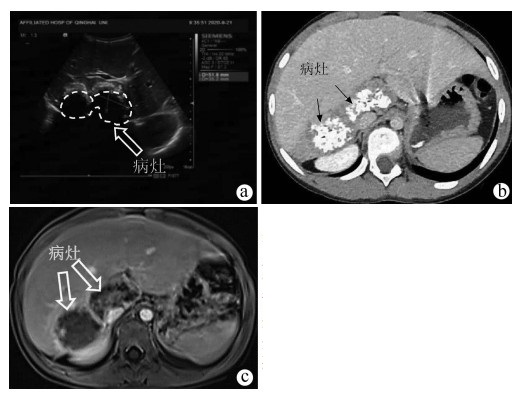

门静脉性胆道病1例报告

姜朋, 王树鹏, 刘亚辉

2022, 38(2): 430-432. DOI: 10.3969/j.issn.1001-5256.2022.02.034

摘要(715) HTML (239) PDF (2686KB)(52)

摘要: